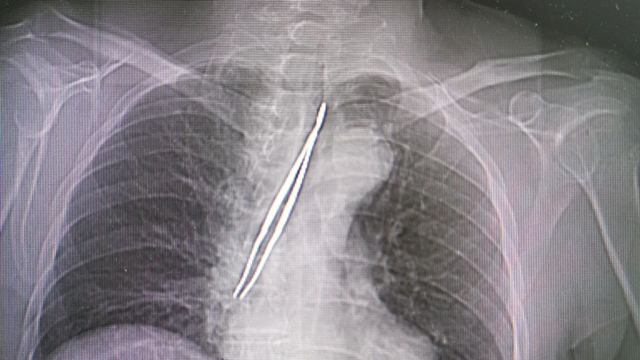

2月20日上午,一位78岁高龄的邹姓患者在家属陪护下匆匆来到来凤县人民医院耳鼻喉科,家属紧张的诉说镊子掉到气管里面了……重症医学科主任邹贻武、呼吸与危重症医学科主任曾圣凯参与会诊后,决定立即为邹大爷行急诊气管异物取出术。〔全文〕